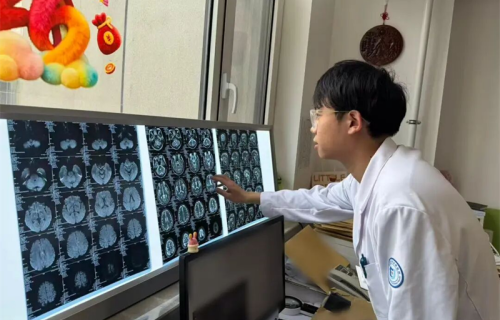

△图片非案例所提及